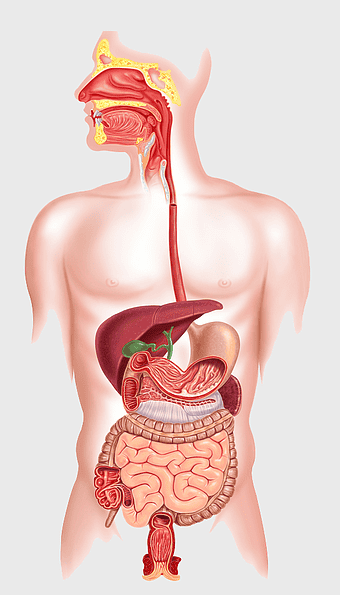

human digestive system, gastrointestinal tract anatomy, liver function, stomach and intestines, digestive health, internal organs diagram, human body systems -

human gastrointestinal tract anatomy, human digestive system illustration, gastrointestinal disease symptoms, human body organ diagram, internal organ visualization, medical anatomy study, digestive health awareness -

human anatomy diagram, digestive system illustration, human internal organs, Homo sapiens muscular system, anatomical art for education, systemic physiology chart, medical biology graphics -

human digestive system illustration, gastrointestinal tract diagram, human body organ system, labeled digestive system, digestive anatomy chart, human internal organs, alimentary canal visualization -

human anatomy illustration, human organ system diagram, human body internal organs, human digestive system, anatomical chart, medical illustration, physiological diagram -

digestive system diagram, gastrointestinal tract chart, human anatomy illustration, small intestine function, digestive process visualization, internal organ layout, metabolic system overview -

human digestive system anatomy, gastrointestinal tract illustration, stomach muscular layer, abdominal organ diagram, digestive health education, medical biology study, internal human body structures -